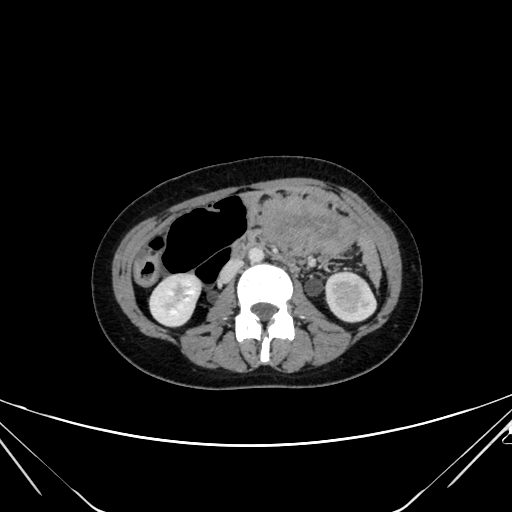

Findings Her entire large bowel was studded with multiple polyps.The rectum and sigmoid had larger polyps as compared to the smaller rest of the bowel which has numerous smaller lesions(Image 1).An ultrasound of her breast was undertaken for the right breasy mass lesion .The ultrasound showed a rather circumscribed lesion in the upper inner quadrant of the right breast splaying fibres of the pectoralis (Black arrowheads in Image 2 ).The lesion was clinically firm to hard and showed no appreciable vascularity on Doppler (Image 3). A USG guided biopsy of the lesion was undertaken which showed spindle cells that were positive for CD99 ,SMA,Desmin and Negative for S100, pan CK, CK 5/6, p63 and CD117,CD 34 . Ki 67 index was less than 3%.(Image 4) . ?eta Catenin showed strong diffuse nuclear positivity(Image 4) . Diagnosis of a spindle cell neoplasm, morphology and immunoprofile favoring Desmoid fibromatosis was given on pathology . Patient eventually underwent prophylactic pancolectomy.She presented a few months post surgery with irregular soft tissue density masses at site of surgical incision on the right rectus (Image 5) and a large intra abdominal mesenteric mass causing distortion and dense bowel adhesions (Image 6). These were diagnosed as fibromatosis on imaging